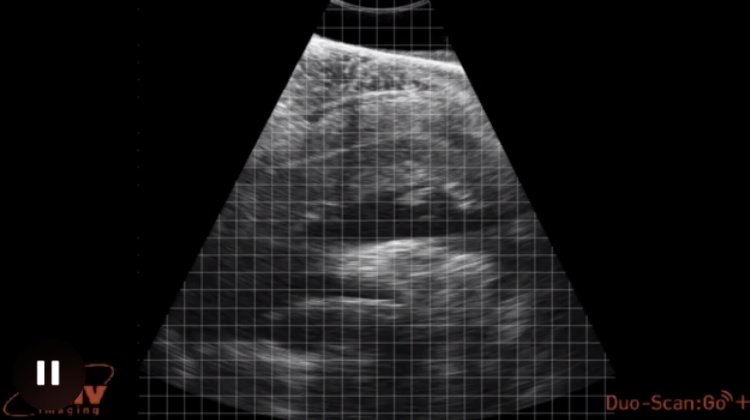

به همین دلیل است که فرومن و تیم از فناوری جدید اولتراسوند بدون تماس برای شناسایی حاملگی در مراحل اولیه در مرجانهای صخرهای استفاده کردهاند که برای حفاظت از گونههایی است که اتحادیه بینالمللی حفاظت از طبیعت آنها را در معرض خطر انقراض فهرست میکند. این فناوری به محققان اجازه می دهد تا آناتومی داخلی حیوان را بررسی کنند و در عین حال استرس را به حداقل برسانند.

این اولین باری است که دانشمندان از اسکنرهای بدون تماس برای به دست آوردن تصاویری از یک پرتو مانتا باردار وحشی استفاده می کنند. در مجموع، فرومن ۸۱ اسکن از ۵۵ مانتای صخره ای آزاد را در مطالعه جدید خود در مجله زیست شناسی ماهی توصیف می کند.

فرومن گفت، اما نتایج "بسیار بسیار نگران کننده" بود. از ۲۱ اسکنی که تصاویری از رحم گرفته شد، هفت زن باردار بودند که تنها چهار مورد از آنها علائم بصری بارداری را نشان می دادند. پنج نفر دیگر - هیچ نشانه بصری بلوغ مانند زخم جفت گیری و رحم بزرگ نداشتند. این یافتهها تأیید میکند که دانشمندان تعداد مادههای بالغ در جمعیت پرتوهای صخرهای در مالدیو را دست کم گرفتهاند.